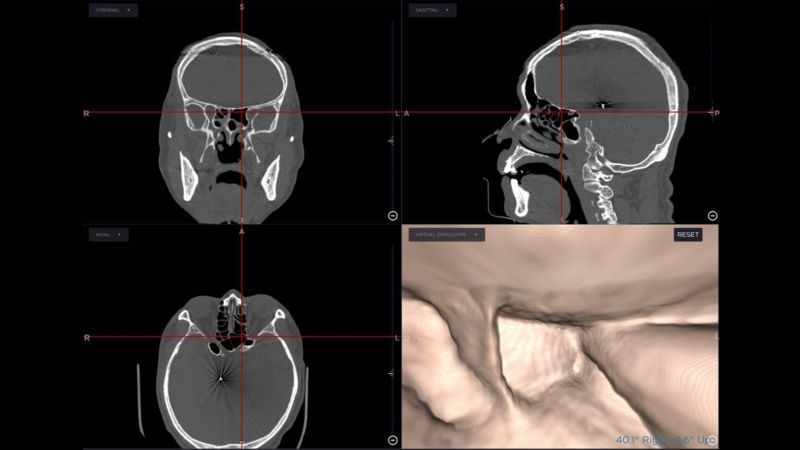

手術導航系統是利用患者的電腦斷層或核磁共振,製作出鼻竇附近的"google map",此地圖中呈現出病人鼻竇細微的解剖結構、病灶、及周遭所有之神經、血管、腦部及眼窩的影像。隨手術進行中,依手術器械所在位置,可即時出現器械鄰近的解剖影像及結構,如同在google map上即時呈現車子所在路況及周遭的建物。使用此系統,在鼻竇的細微且複雜的結構中,開刀時就降低迷路的風險;器械可精準切除病灶,避免傷害鄰近的重要器官,對於患者與醫療團隊都是一大利器。鍾從得主任以其使用手術導航系統十六年的經驗裡,不僅在復發之鼻竇炎、鼻息肉的內視鏡手術,並於鼻竇鄰近或腦部眼窩之病變,如黏液囊腫、顱底腫瘤、復發之鼻咽癌等手術中,藉由導航系統的精準定位,確實提高了手術的成功率及在病人的安全性上提供莫大保障。